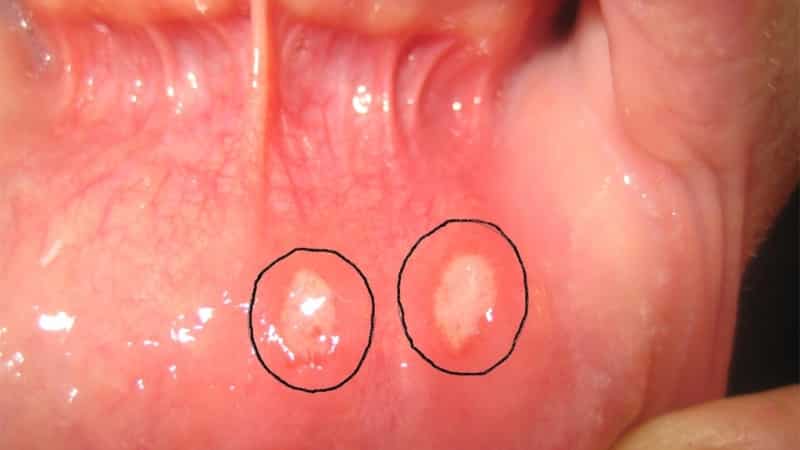

- эрозивно-язвенная форма ‒ характеризуется выраженной болезненностью, усиливающейся при разговоре и приеме пищи, покраснением и отеком слизистой рта, образованием водянистых пузырей, которые при вскрытии превращаются в эрозии с фибринозным налетом. Также могут возникать контактные кровотечения, першение и дискомфорт в горле.

- афтозный стоматит ‒ вызывается вирусом герпеса и проявляется образованием пузырей с мутной жидкостью на слизистой рта, которые затем превращаются в язвы. Также могут наблюдаться отек и покраснение слизистой, повышение температуры, общая слабость, снижение аппетита и вялость;